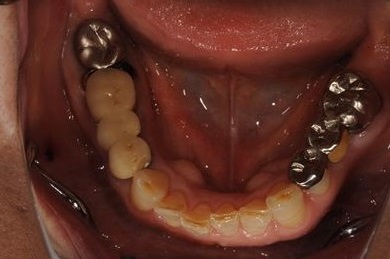

インプラントの症例写真 IMPLANT

骨再生スピードインプラント治療+セラミック治療

| 性別/年齢 | 女性 / 58歳 | ||||||||||||||||||||||||||||||||

| 主訴 | 左上前歯となりがゆらついている。他院でインプラントが必要と言われ、相談に来ました。 | ||||||||||||||||||||||||||||||||

| 治療方針 | 骨再生法によりインプラント治療を可能にする。抜歯と同時にインプラント埋入を行い、治療期間を短縮する。 | ||||||||||||||||||||||||||||||||

| 治療内容 | インプラント3本(抜歯即日スピードインプラント、GBR)、メタルボンドセラミッククラウン1本、ハイブリッドセラミッククラウン4本(ハイブリッドセラミック用土台1本) | ||||||||||||||||||||||||||||||||